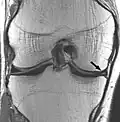

| Proton density weighted | PD | Long TR (to reduce T1) and short TE (to minimize T2).[7] | Joint disease and injury.[8]

Proton density (PD)- weighted images are created by having a long repetition time (TR) and a short echo time (TE).[36] On images of the brain, this sequence has a more pronounced distinction between grey matter (bright) and white matter (darker grey), but with little contrast between brain and CSF.[36] It is very useful for the detection of arthropathy and injury.[37]